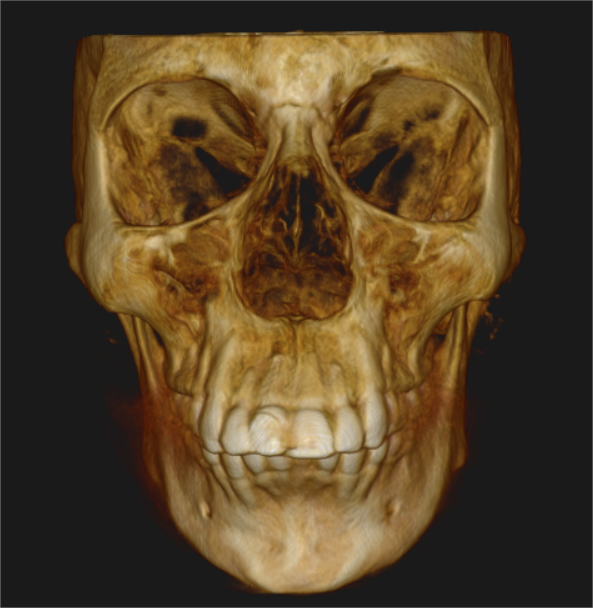

Cone Beam Computed Tomography (CBCT)

Special 3D imaging technique that provides detailed images of teeth, jaws, nerves, and surrounding structures. CBCT is quick, accurate, and offers 3 Dimensional knowledge compared to normal X-rays, ensuring better care for complex dental issues.

Accurate diagnostic features of various pathologies like cysts and tumors for better treatment planning

Endo Analysis of the tooth and related pathology

TMJ Assessment